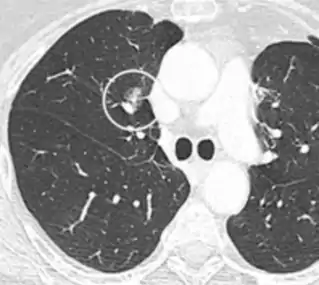

A lung nodule or pulmonary nodule is a relatively small focal density in the lung. A solitary pulmonary nodule (SPN) or coin lesion,[1] is a mass in the lung smaller than three centimeters in diameter. A pulmonary micronodule has a diameter of less than three millimetres.[2] There may also be multiple nodules.

CT scan

For incidentally detected nodules on CT scan, Fleischner Society guidelines are given in table below. For multiple nodes, management is based on the most suspicious node.[8] These guidelines do not apply in lung cancer screening, in patients with immunosuppression, or in patients with known primary cancer.[8]